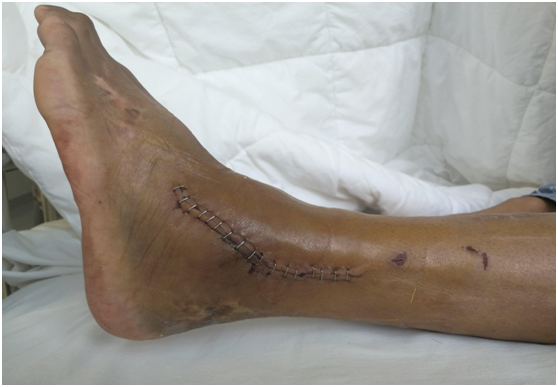

傳統(tǒng)手術(shù)的切口

關(guān)節(jié)鏡手術(shù)的切口